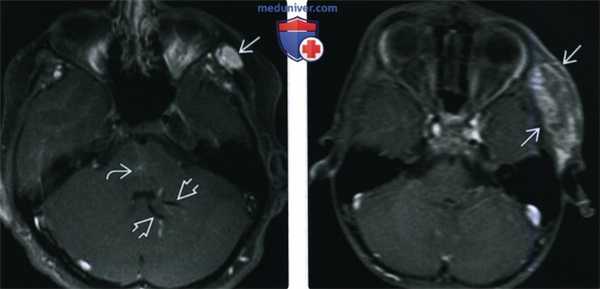

(Слева) При аксиальной МРТ Т1ВИ С+ FS в левой височной мышце визуализируется венозная мальформация, умеренно накапливающая контраст; в левой гемисфере мозжечка определяется врожденная венозная аномалия, в области моста мозга также визуализируется вероятная венозная аномалия меньшего размера или телеангиэктазия.

(Справа) При аксиальной МРТ Т1ВИ С+ FS в левой височной ямке визуализируется венозная мальформация, неравномерно накапливающая контраст.